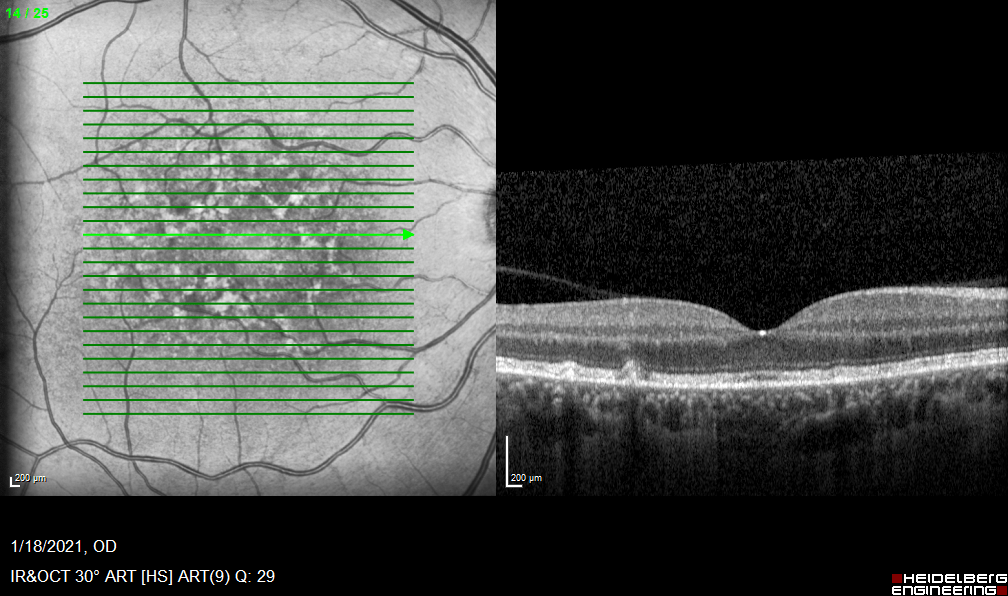

Case#1-PVH

Slowly progressive vision loss in a patient with MS.